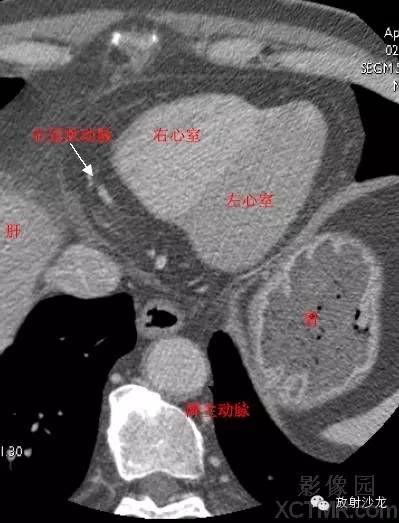

LV -Left Ventricle左心室

RV -Right Ventricle右心室

D. Aorta-Descending Aorta降主动脉

RCA -Right Coronary Artery 右冠状动脉